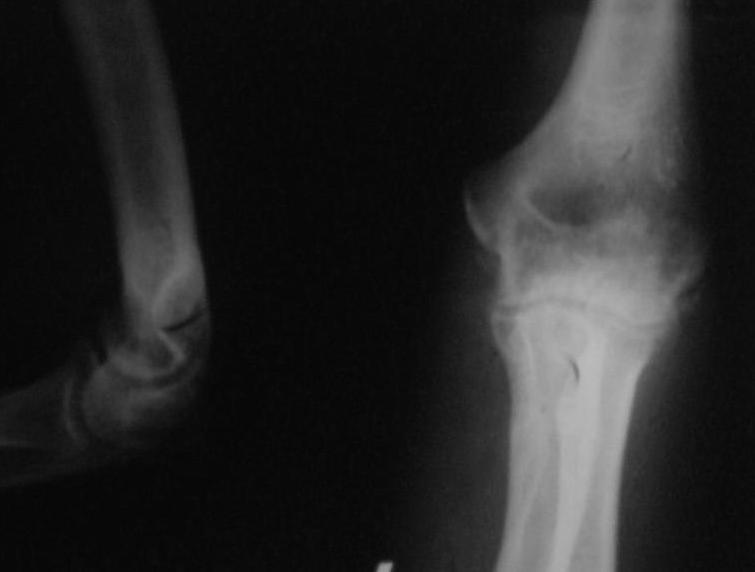

Поступил пациент, 47 лет. травма 15 сентября - вывих предплечья, репозиция. Фиксация 1 месяц.

До настоящего времени не обращался. Вот рентенограммы на 2-й и 3-й месяцы после травмы. Неврологии нет. Имеется контрактура локтевого сустава (сгибиние 90, разгибание 120). На снимках что-то похожее на гетеротопические оссификаты, такое впечатление. Как лучше восстановить функцию, возможно ли применить редрессацию? Все-таки локтевой сустав "капризный".